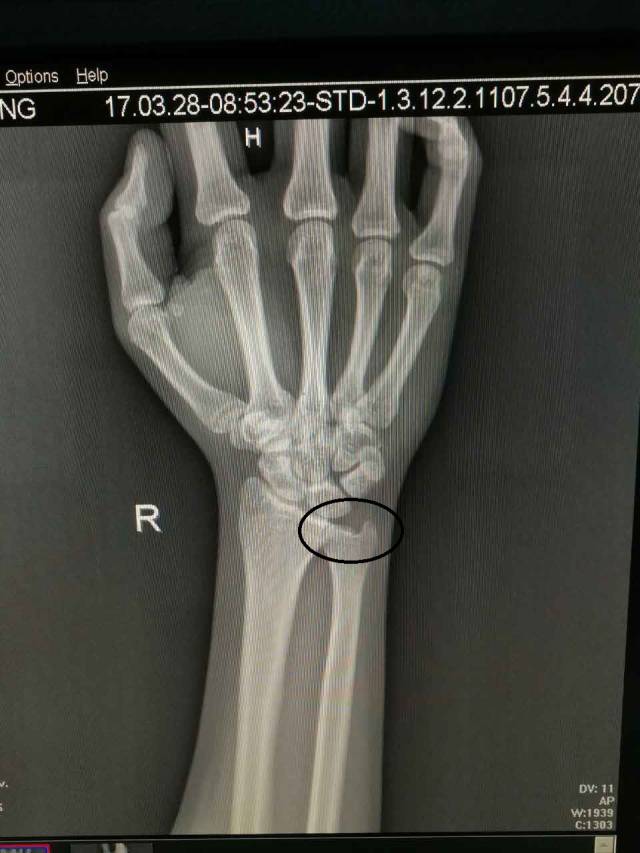

(图中所打圈的位置就是下尺桡关节)

对于没有经验的人来说,很多人会以为损伤是撞到“麻经”了,丝毫没有觉察,其实已经下尺桡关节脱位了。其实下尺桡关节脱位的伤害不亚于骨折,如何自测有没有下尺桡关节脱位呢,笔者告诉大家一定要注意以下4点: